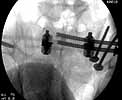

Patient was prone for procedure, as I thought too difficult to fix the wing in lateral position. Of course the repair of wing was easy, but reduction of SI very demanding. The Floro images document the residual lack of reduction. That was the closest I could get it using 6mm joystick in wing, and clamp on sacrum and clamp through notch.  The fixation was (initially) rigid. Anterior ex fix with supra-acetabular pins was placed due to condition of soft tissues, massive "beer-belly" overhanging the crest.

5. Your caudal iliosacral screw is/was in his spinal canal...it's low and posterior and the lateral fluoro image confirms this...a postop CT will show it (or it's trail at this point)...canal screws do not hold.